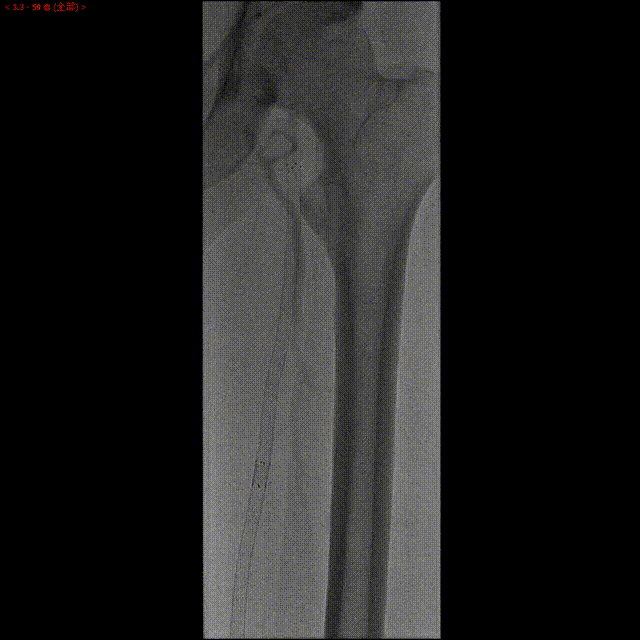

现病史:患者于4年前出现活动后双下肢疼痛。2018年5月下肢动脉造影示双侧股浅动脉慢行完全性闭塞,于右侧股浅动脉植入支架1枚,左股浅动脉植入支架2枚,2019年5月造影示左股浅动脉支架内闭塞,行球囊扩张术复通。2021年12月下肢彩超示双侧股浅动脉支架闭塞,右侧股浅动脉球囊扩张术后复通。

左侧股浅动脉支架内重度狭窄,支架出口闭塞,股深动脉侧支供应股浅动脉远段。

此患者为73岁老年男性,合并糖尿病,平时血糖控制不佳。股浅动脉支架植入术后,反复出现支架内再闭塞。此次左侧股浅动脉严重狭窄,支架内全程狭窄,远端支架出口闭塞,借侧支循环显影。